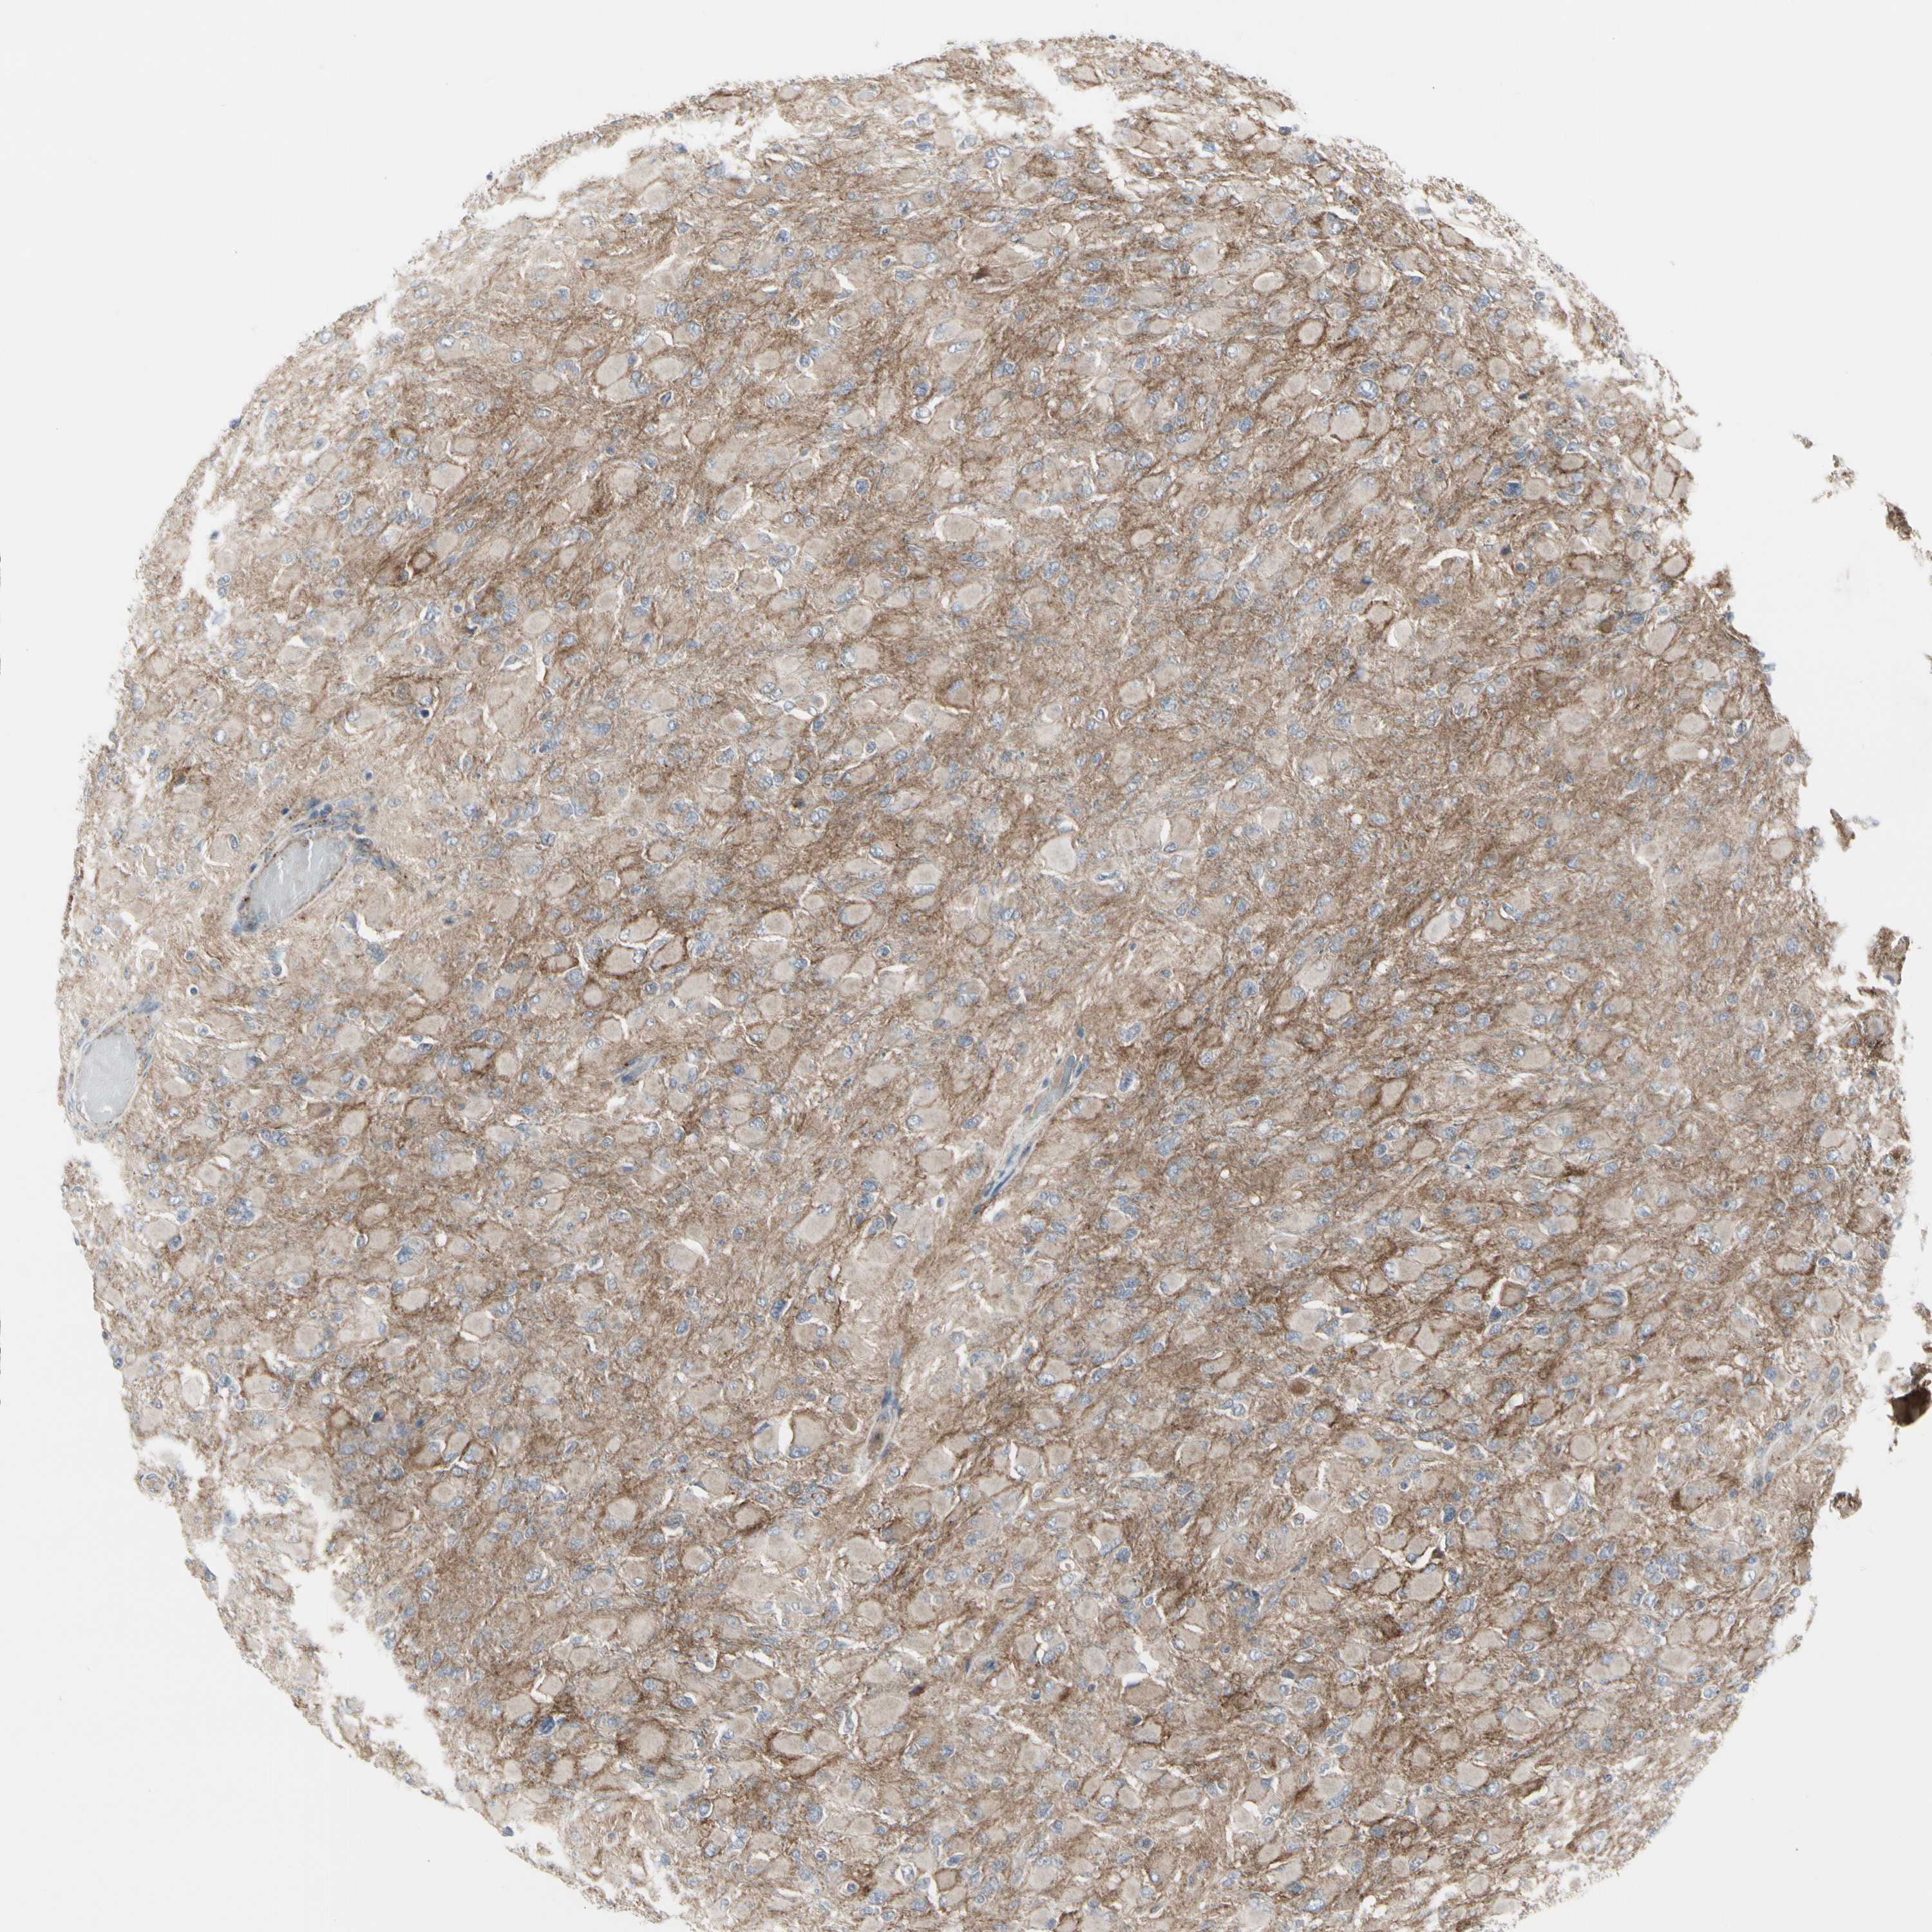

GLIOMA - Protein expressioni

A mouse-over function shows sample information and annotation data. Click on an image to view it in a full screen mode. Samples can be filtered based on level of antibody staining by selecting one or several of the following categories: high, medium, low and not detected. The assay and annotation is described here.

Note that samples used for immunohistochemistry by the Human Protein Atlas do not correspond to samples in the TCGA dataset.

Antibody stainingi

Antibody staining in the annotated cell types in the current human tissue is reported as not detected, low, medium, or high, based on conventional immunohistochemistry profiling in selected tissues. This score is based on the combination of the staining intensity and fraction of stained cells.

Each image is clickable and will lead to virtual microscopy that enables deeper exploration of all samples and also displays staining intensity scores, fraction scores and subcellular localization as well as patient and tissue information for each sample.

Antibody HPA008763

Antibody HPA028747

Antibody CAB019394

Staining

High

Medium

Low

Not detected

Intensity

Strong

Moderate

Weak

Negative

Quantity

>75%

75%-25%

<25%

None

Location

Nuclear

Cytoplasmic/membranous

Cytoplasmic/membranous,nuclear

Glioma, malignant, High grade

Glioma, malignant, Low grade